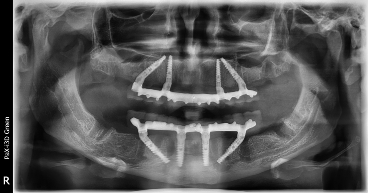

All-on-4 на рентгеновских снимках

От оценки полной или частичной адентии (полного или частичного отсутствия зубов) проводится анализ и плотности костной ткани. Основная резобция (убыль) костной ткани происходит в дистальных отделах.

Верхняя и нижняя челюсть имеют разные навигационные ориентиры для установки дистальных имплантатов (установленных под углом) и глубины погружения. На верхней челюсти ограничением является ориентир, где отчетливо видно кривую петлю синуса гайморовой пазухи (мембрана Шнейдера). Для того, чтобы пазуха осталась целостной, не перфорированной, мы не выходим за этот ориентир при работе с костью и инсталляции имплантата.

Также на верхней челюсти важны условия погружения имплантата и плотность костной ткани. Начинаем погружение в губчатую костную ткань, так называемую трабекулярную костную ткань, плотность кости в этом слое всегда средняя и минус.

Далее мы проходим базальный слой костной ткани и на заданной глубине погружения имплантата заякореваемся в плотном слое, называемым кортикальный (панцирный).

На верхней челюсти для достижения ТОРКа (стабильности имплантата, относительно костной ткани,) необходима бикортикальная установка имплантата.

ТОРК – это величина стабильности имплантата при конечном погружении в кость (в гребень), определяется динамометрическим ключом, должна быть не менее 35-40 H/Cм2.

С нижней челюстью процесс более прагматичный в связи с тем, что конгломерат костной ткани не имеет пазух и является целостным. Установка происходит внутри двусторонних ментальных отверстий (окончаний нижнего альвеолярного нерва). Определение вертикальной и горизонтальной резорбции на нижней челюсти корректирует длину и диаметр установленных имплантатов. Костная ткань на нижней челюсти имеет среднюю плотность и выше.